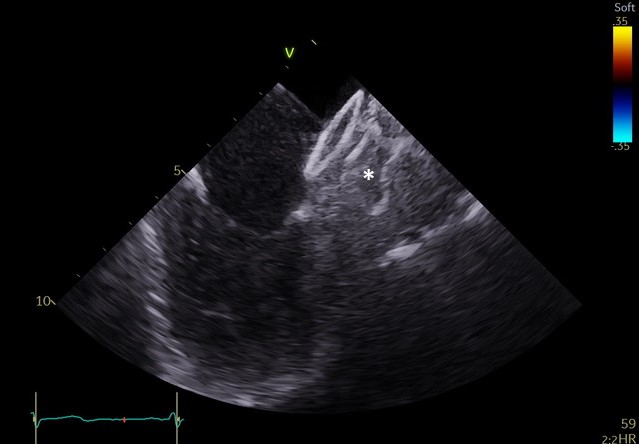

Specjaliści z Pracowni Kardiologii Inwazyjnej I Kliniki Kardiologii UCK przeprowadzili 3 zabiegi zamknięcia uszka lewego przedsionka (ang. LAAO – left atrial appendage occlusion) z wykorzystaniem systemu echokardiografii wewnątrzsercowej (ang. ICE – intracardiac echocardiography).

– U części pacjentów kwalifikowanych do LAAO ryzyko związane z wykorzystaniem obrazowania metodą TEE jest zbyt wysokie ze względu na poważne zmiany chorobowe przełyku. To dotychczas uniemożliwiało wykonanie zabiegu. Obrazowanie metodą ICE pozwala na bezpieczne wykonanie zabiegu zamknięcia uszka lewego przedsionka również w tej grupie chorych, ponieważ specjalną sondę ultrasonograficzną wprowadza się nie do przełyku, lecz przez układ żylny pacjenta, bezpośrednio do jam serca – mówi dr Dariusz Ciećwierz, koordynator Pracowni Kardiologii Inwazyjnej I Kliniki Kardiologii UCK z I Katedry i Kliniki Kardiologii GUMed. – Dodatkową korzyścią tego rozwiązania jest większy komfort pacjenta w trakcie zabiegu, dzięki czemu można uniknąć sedacji czy znieczulenia ogólnego.

– Mogą one powodować ciężkie krwawienia, co sprawia, że u części takich pacjentów nie ma możliwości leczenia przeciwzakrzepowego i proponuje się zabieg LAAO. Z drugiej strony wprowadzenie sondy ultrasonograficznej do zmienionego chorobowo przełyku samo w sobie wiąże się z wysokim ryzykiem wystąpienia krwawienia z żylaków. U takich chorych mamy obecnie możliwość wykonania zabiegu z zastosowaniem obrazowania metodą ICE – tłumaczy prof. Marcin Fijałkowski, koordynator Oddziału Chorób Strukturalnych I Kliniki Kardiologii UCK z I Katedry i Kliniki Kardiologii GUMed.

W ramach przygotowania do wprowadzenia metody do praktyki klinicznej w UCK, zespół zabiegowy miał możliwość przetrenowania jej zastosowania na zaawansowanym symulatorze w Centrum Symulacji Sercowo-Naczyniowej GUMed. Zabiegi wykonano u dwóch pacjentów z zaawansowanymi żylakami przełyku z powodu marskości wątroby oraz u pacjentki z wrodzoną naczyniakowatością krwotoczną (choroba Rendu-Oslera-Webera). Nadzór merytoryczny w trakcie pierwszych przeprowadzonych zabiegów zapewnił dr hab. Witold Streb, kardiolog ze Śląskiego Centrum Chorób Serca w Zabrzu.